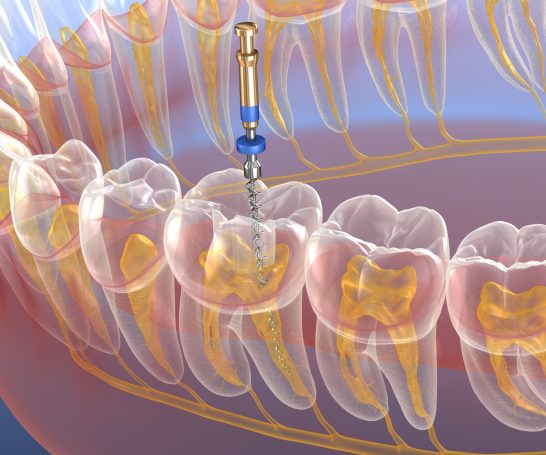

Leistungen

Dank mehreren Behandlern können wir Ihnen ein großes Spektrum an Behandlungen direkt an unseren Standorten zur Verfügung stellen.